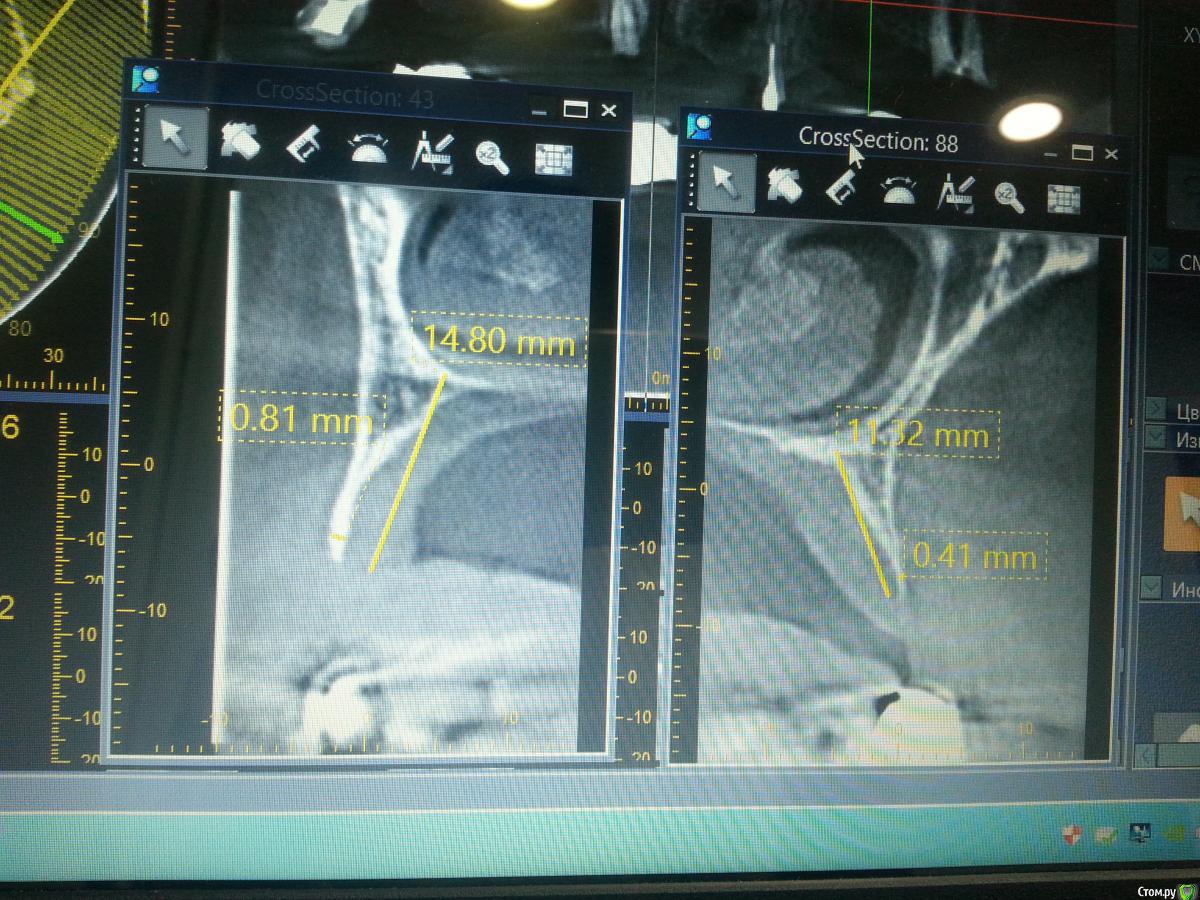

faity Опубликовано 29 мая, 2015 Поделиться Опубликовано 29 мая, 2015 На нижней челюсти деструкции нет. Панорама из кт по этому такая картинка. а можно срезы? слишком подозрительно располагаются зубы Ссылка на комментарий

uzstom Опубликовано 29 мая, 2015 Автор Поделиться Опубликовано 29 мая, 2015 а можно срезы? слишком подозрительно располагаются зубыhttp://images.vfl.ru/ii/1432891106/0fd29afe/8881447_m.jpg Ссылка на комментарий